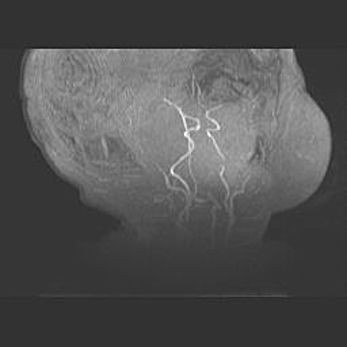

Множественные кисты обоих полушарий головного мозга, наибольшая из них в правой затылочной области. Ассиметричная атрофическая гидроцефалия.

Возраст: 7 месяцев

Вес: 5660 г

Пол: мужской

Окружность головы: 41,5 см

Срок гестации: 28-29 недель

Кисты головного мозга развиваются в результате многоочаговых некрозов вещества мозга и возникают вследствие перенесенной перинатальной инфекции, менингитов, энцефалитов, асфиксии, родовой травмы, расстройств мозгового кровообращения различного генеза. Образованию кист в веществе головного мозга плодов и новорожденных способствуют такие факторы, как высокое содержание в нем воды, недостаточная (или отсутствие) миелинизация и слабая астроглиальная реакция на повреждение.

Кисты могут сочетаться с гидроцефалией и другими поражениями головного мозга.